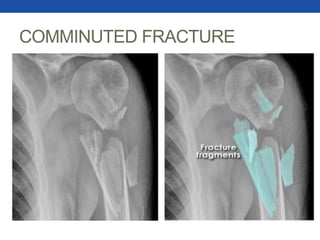

COMMINUTED FRACTURES

•Fractures resulting in

multiple bone fragments.

•Some specific examples

include butterfly fractures

and segmental fractures.

COMMINUTED FRACTURE